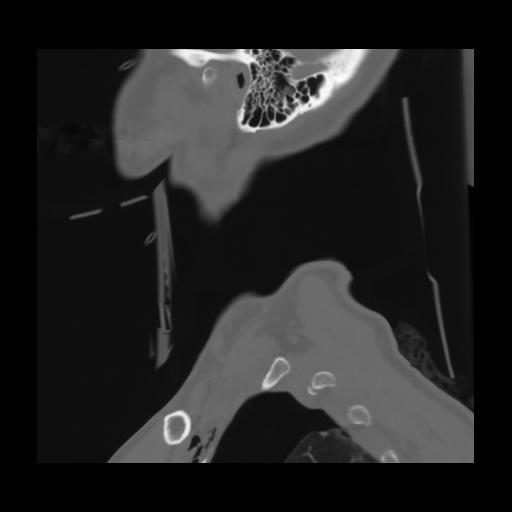

14 P.BLANDAS,,Sagittal,2.000,P.BLANDAS,Sagittal,